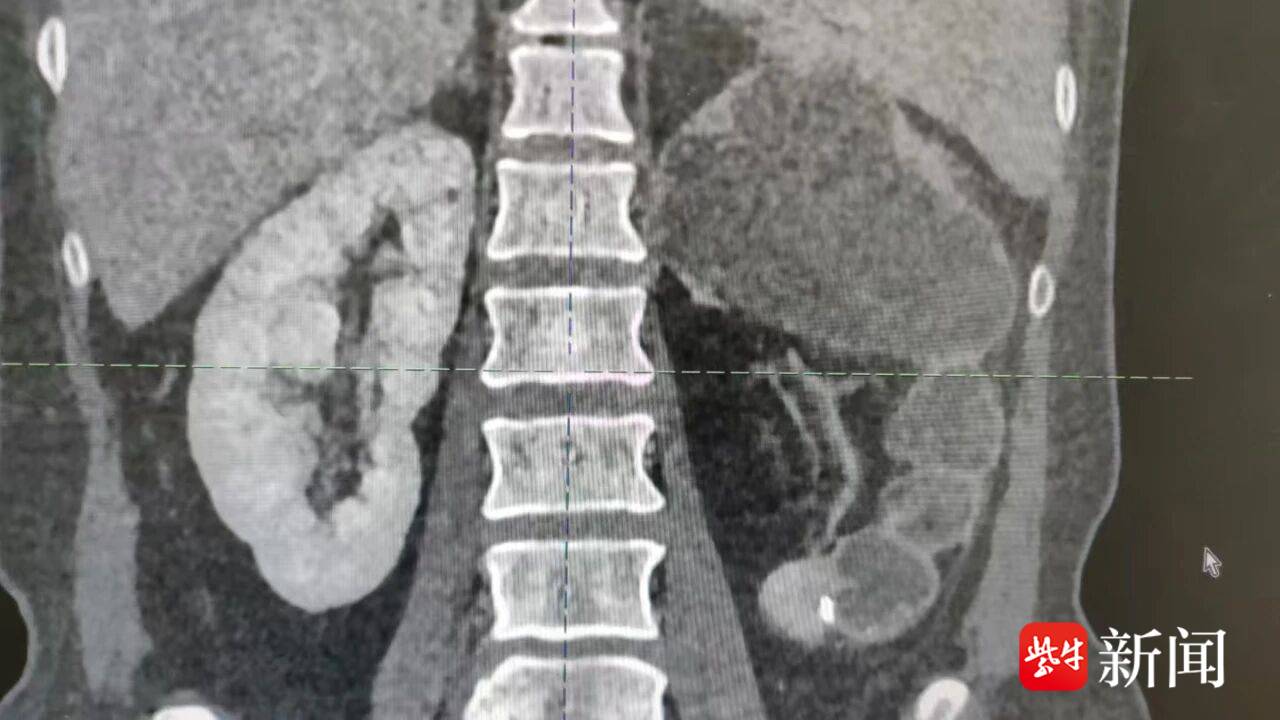

患者CT影像。通讯员供图

入院后,王荣团队对患者进行了全面评估。影像学显示:左肾血流灌注严重不足,滤过功能近乎消失。“结核菌对肾脏的破坏是不可逆的。若继续拖延,感染可能波及其他器官。”王荣解释。经过多学科充分讨论与术前精细评估,团队最终决定为患者实施腹腔镜下左肾及部分输尿管切除术。